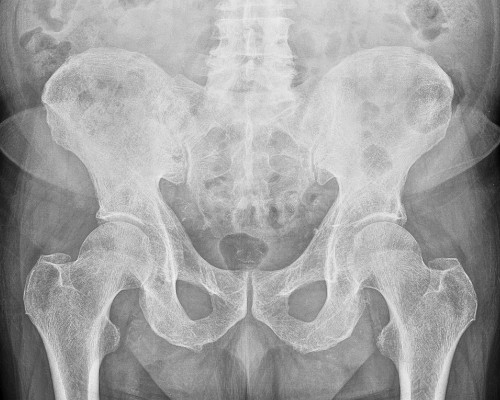

Hip Fractures

When the hip breaks, life comes to a sudden halt. Whether due to a fall or osteoporosis, Dr. Mehta offers expert surgical input to help you to restore stability, reduce pain, and help you regain independence step by step.